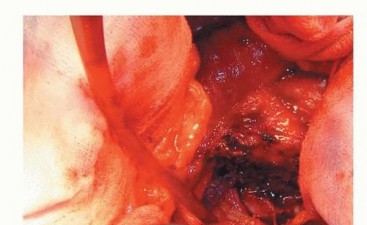

صورة طبية: نصف مفصل الورك: دليلك الشامل لدواعي الاستخدام والأنواع في صنعاء